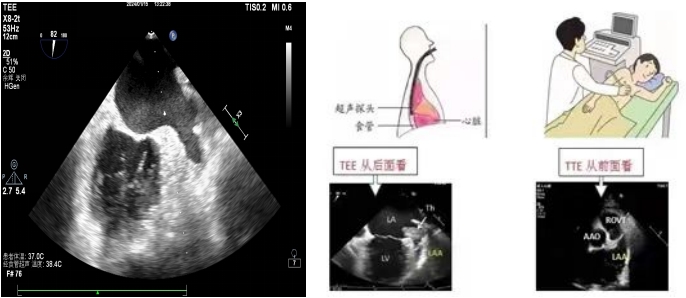

左心耳位于左心房的偏后上部分,大部分情況下被左心房主體部分遮擋,常規(guī)的經(jīng)胸超聲心動(dòng)圖(TTE)很難清晰顯示。TEE是超聲探頭置入食道內(nèi),從心臟的后方進(jìn)行檢查,縮短了超聲探頭與心臟及距離,避免了肺氣干擾、肋骨遮擋等弊端,可直觀的從左心房看到左心耳,排查左心耳內(nèi)有無血栓。目前我院開展了常規(guī)經(jīng)食道超聲心動(dòng)圖和無痛經(jīng)食道超聲心動(dòng)圖檢查。